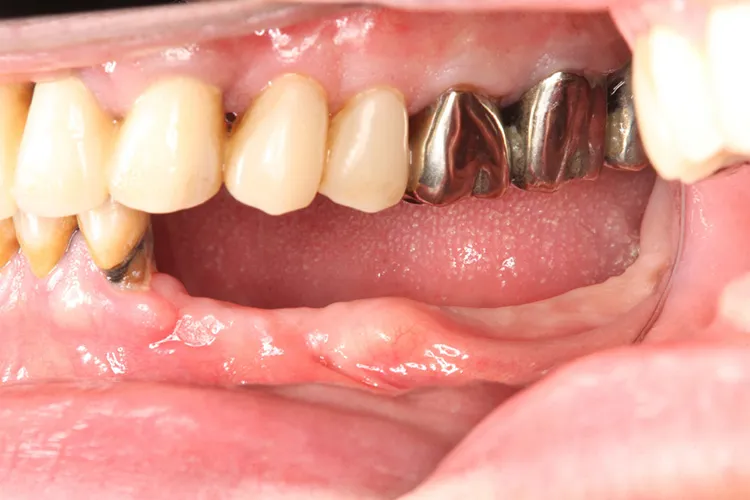

治療前

治療後

レントゲン画像

治療内容

左下5本欠損した部分をインプラント3本埋入して5本ブリッジで治したケースです。なかなかインプラントに踏み切れず、長い間入れ歯を使っておられましたが、噛みごたえがなく好きなものが食べれない上に、度々歯茎が痛んでは調整の繰り返しで快適に過ごすことができず、QOLの向上のためインプラント治療を決断されました。今ではなんでも食べれるとのことで、入れ歯で我慢しないでもっと早くインプラントにすればよかったと言っておられます。